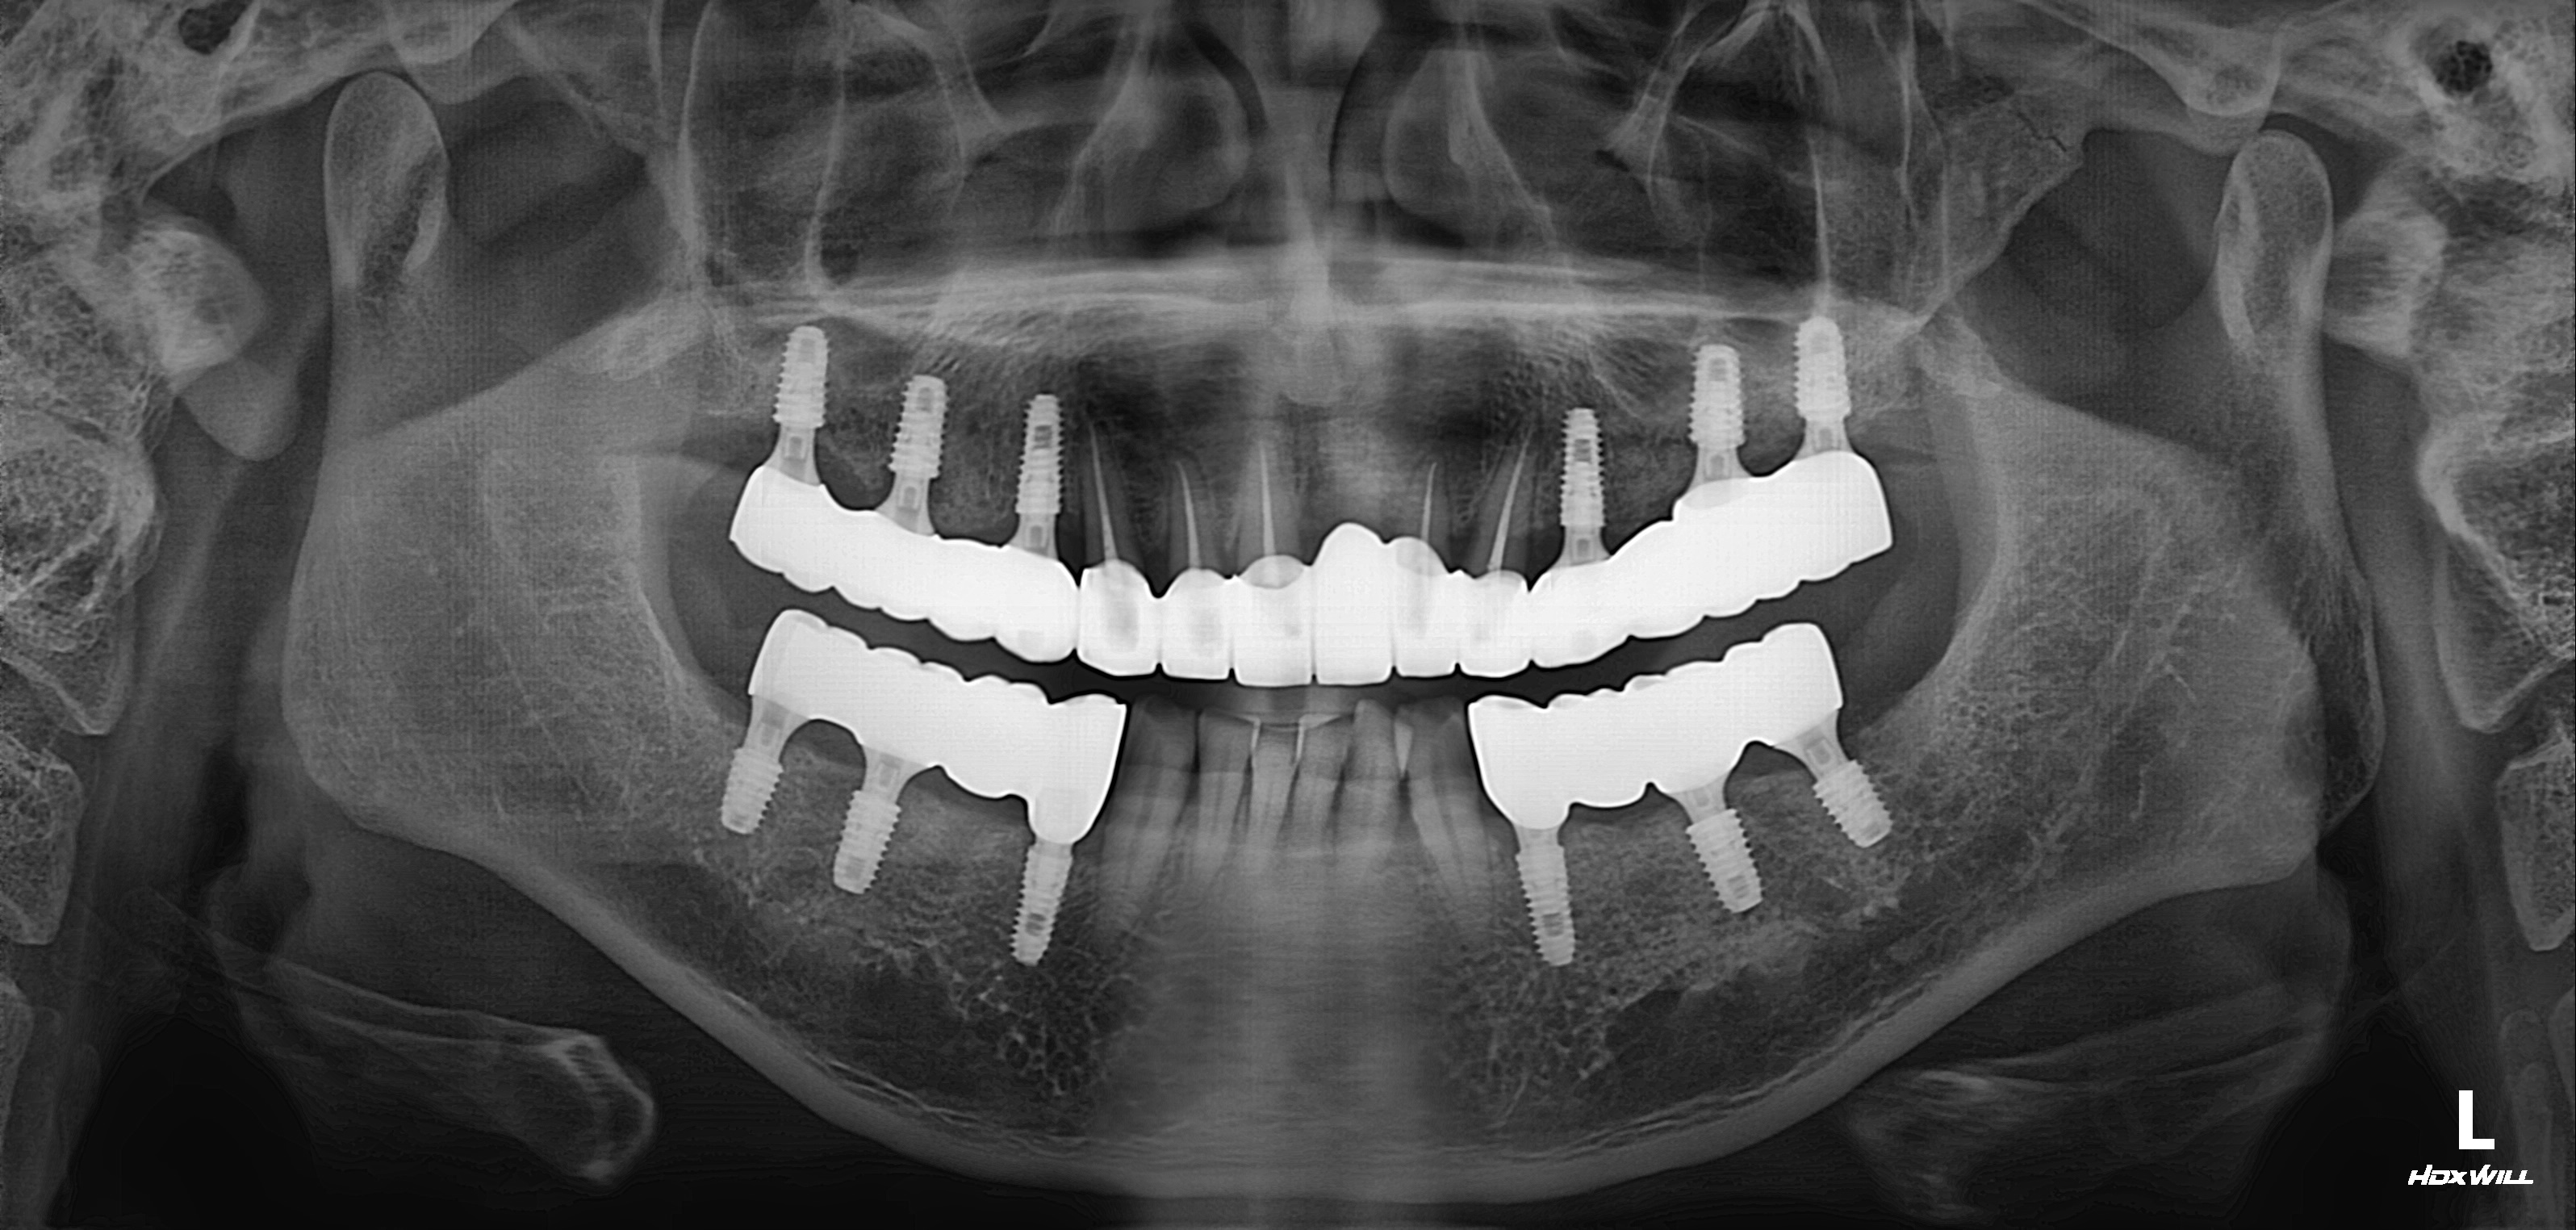

수술 전

수술 후

상악 임플란트 식립사례

전후사진